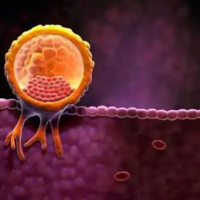

2、试管促排卵

达必佳的药物成分能够刺激女性卵巢,然后诱发排卵,其目的是为了获得更多的成熟的卵子。